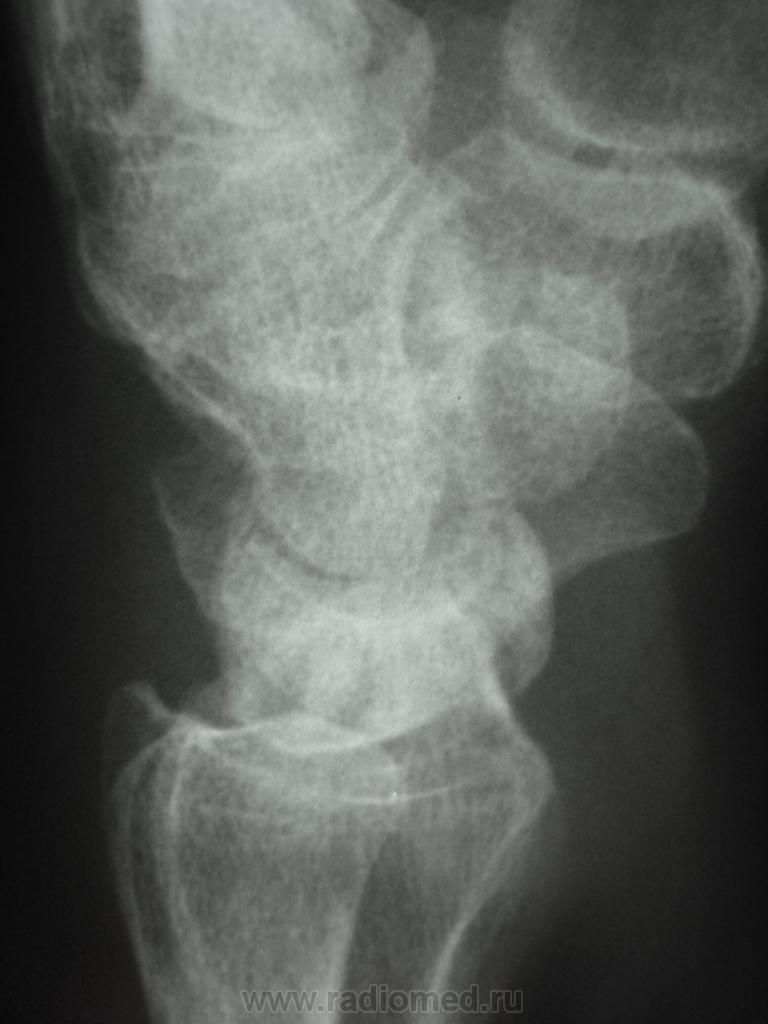

женщина, 1956 года рождения, жалобы на боли в правой лучезапястном суставе в течение полу года, травму отрицает. Кроме остеохондропатии полулунной кости в голову ничего не приходит. Ваше мнение коллеги))))))))

Интересный случай.

Скоро наступит патологический перелом...

Остеохондропатия - удел детского возраста. Здесь, думаю, правильнее говорить об асептическом некрозе.

Остеохондропатия (греч. οστεοχονδροπαθια) – асептический некроз губчатой кости, протекающий хронически и дающий осложнения в виде микропереломов. Остеохондропатии являются следствием местных расстройств кровообращения, возникающих в результате воздействия различных факторов: врождённых, обменных, травматических и др.